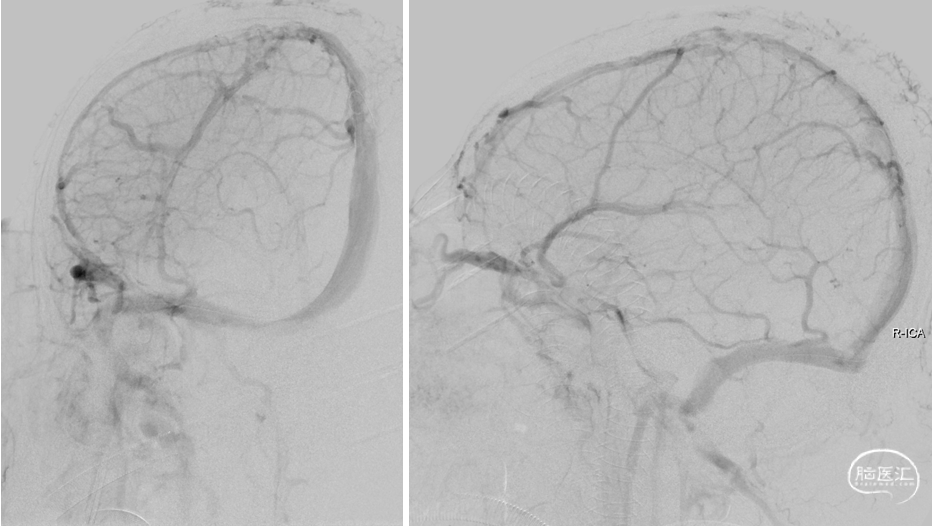

复查造影:上矢状窦显影明显改善,右侧横窦及乙状窦显影良好,静脉回流良好。行平板CT颅内未见出血。

复查造影:上矢状窦显影明显改善,右侧横窦及乙状窦显影良好,静脉回流良好

颅内正侧位造影:上矢状窦显影明显改善,右侧横窦及乙状窦显影良好,静脉回流良好